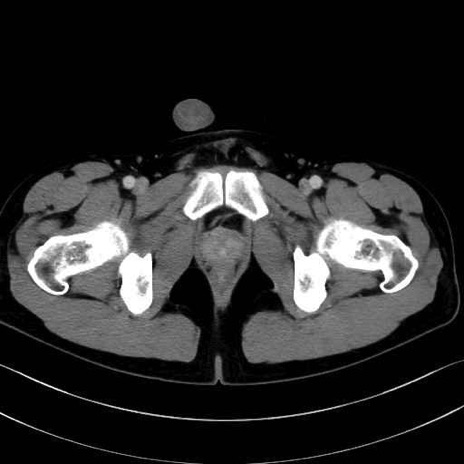

長内転筋(Adductor longus muscle)のCT画像の解剖

長内転筋 (Adductor longus)

短内転筋 (Adductor brevis)

大内転筋・小内転筋 (Adductor magnus / Adductor minimus)